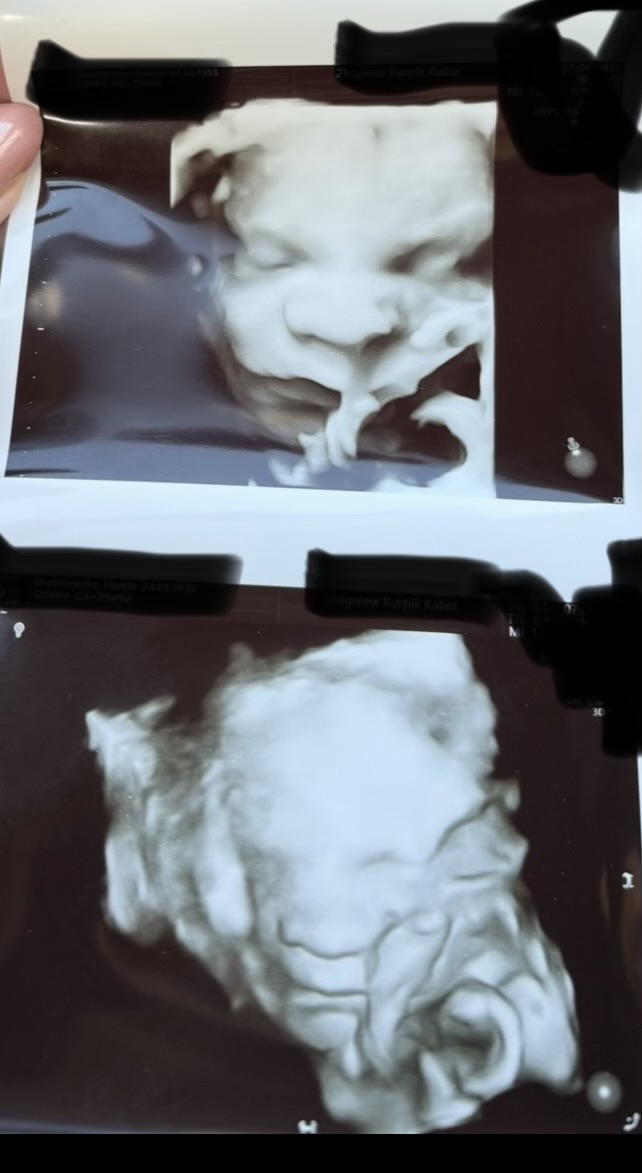

Musi mieć głowicę do badania 3d. U mnie najładniejsze zdjęcia wychodziły pomiędzy 24 a 30 tc później już był tak wkręcony w dół macicy, że nie było jak podejść głowicą, żeby zrobić ładne zdjęcie. U mnie zawsze jak tylko była okazja na ładne zdjęcie to pani doktor zmieniała głowicę i pokazywała nam co tam dziecko wyrabia w 4d i od razu robiła zdjęcie w 3d.

Taka wskazówka- dużo ładniej te zdjęcia wychodzą jak zrobisz sobie zdjęcie ekranu. Moja pani doktor mi to powiedziała i rzeczywiście porównując zdjęcie ekranu a wydruk to pierwsze daje dużo lepszą jakość.Wiadomość wyedytowana przez autora: 8 kwietnia, 14:30

Nowa31 wrote:U nas po wizycie wszystko super ❤️ wszystko jest ok więc odetchnęłam z ulga , udało nam się jakąś fotkę złapać 🥹 ale ciężko było bo zasłonił się pępowina i rączki trzymał na buzi ale jakoś go tam rozruszaliśmy i trochę się pokazał ♥️

Co do zdjęć, to my najładniejsze mamy z 1 prenatalnych. Dokładnie widać było już nosek, rączki i ustka ☺️

Z drugich takie sobie, całe rozmazane, bo fikał jak szalony i ustawił się tyłem 😅

16.04 mamy trzecie prenatalne i liczymy, że zobaczymy buzię bobaska w całej okazałości 🤗🥰❤️

Jablkova - my najładniejsze to teraz 😂 te pierwsze były spoko a na drugich to tak jak twój - wypiął się na nas 😂😂